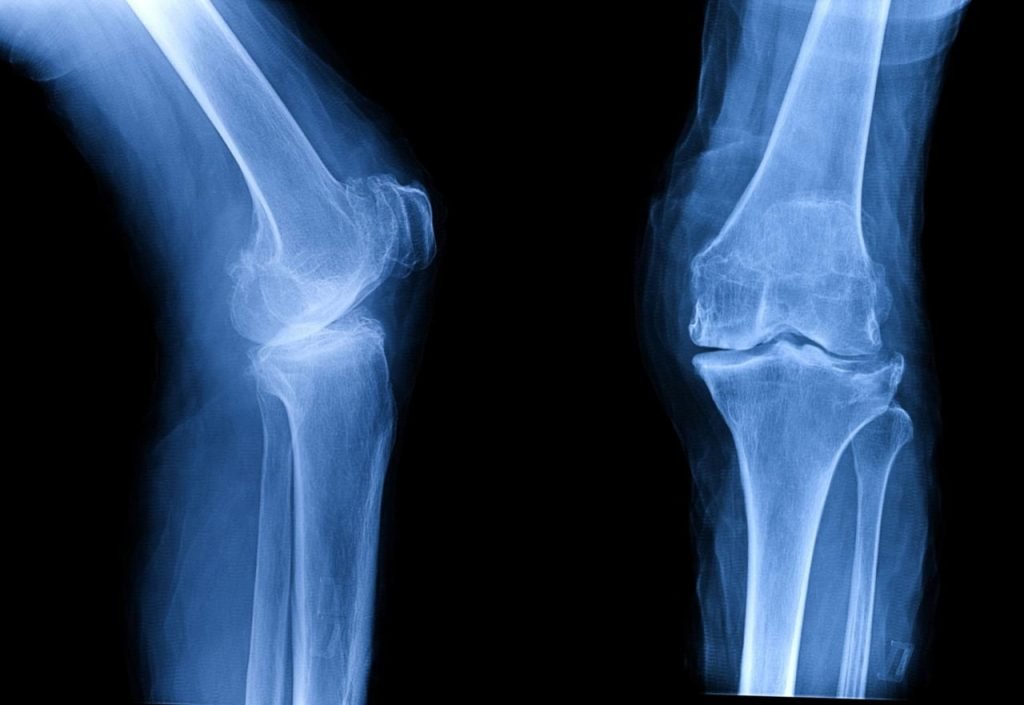

What are the different types of knee surgeries?

Common types include:

- Total Knee Replacement (TKR) – replacing entire joint

- Partial Knee Replacement – only damaged part replaced

- Arthroscopy – minimally invasive (small cuts, faster recovery)

- ACL Reconstruction – ligament repair for sports injuries